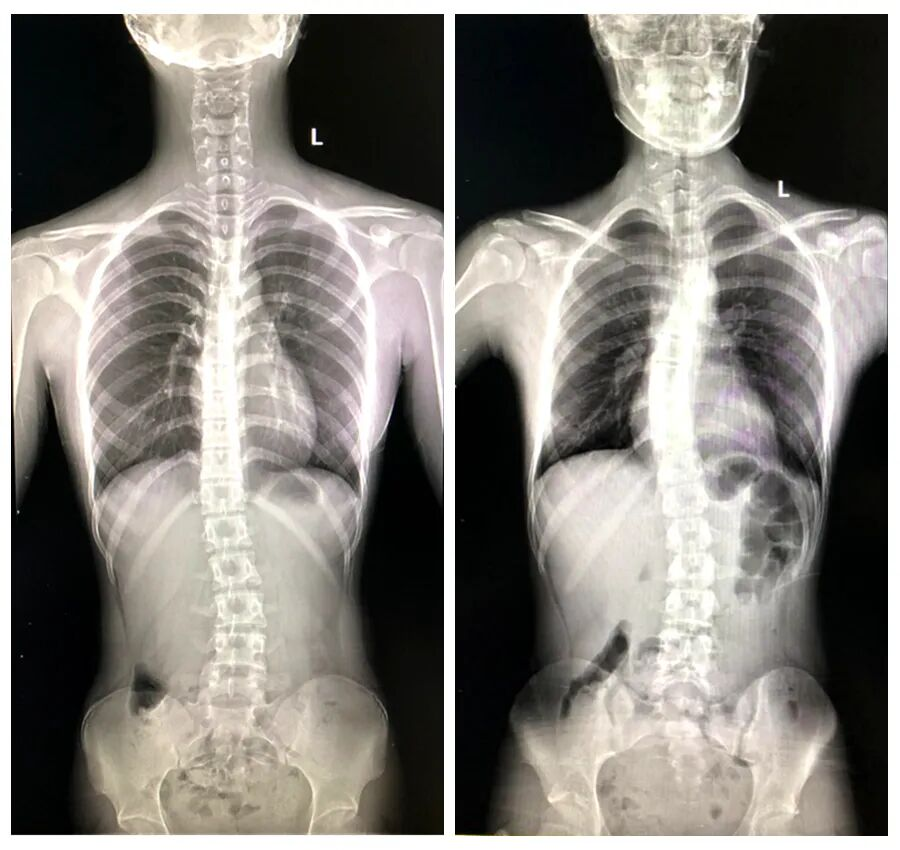

▲多功能DR脊柱全长片,脊柱侧弯畸形

脊柱侧弯是青少年常见骨骼问题,尤其在生长发育期,畸形进展风险高。不仅影响体态,更可能压迫内脏,导致功能障碍。全脊柱X线摄影是诊断脊柱侧弯的金标准,可清晰显示脊柱全长曲线,为矫形治疗提供精准依据。

多功能动态平板DR:全脊柱摄影的利器

放射科引进的高性能多功能动态平板DR,具备全身拼接功能,实现无缝全景成像,大幅提升检查效率和舒适度,尤其适合青少年群体全脊柱摄影。该设备不仅能一次性完成脊柱全长拍摄,避免多次曝光,还支持动态观察,辅助医生分析侧弯角度、旋转程度,为个性化治疗方案奠定基础。